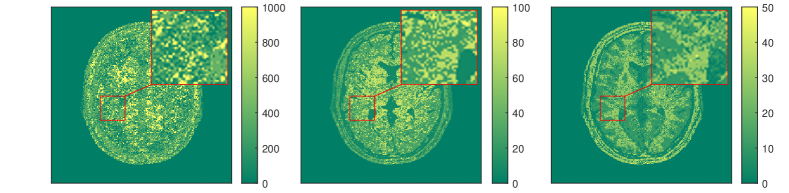

The results for each of the above mentioned algorithms can be found in Figures 3 and 4. We use the MRF reconstruction as initialization for the L-M algorithm, and compare that with the result of the BLIP algorithm when using a relatively refined dictionary. The advantage of integrated-physics approaches is evident by checking the reconstructions in Figure 3 as well as quantitatively by looking at the error maps in Figure 4. In this example, we have used a time series of the 1/8 Cartesian-subsampled k-space data (Fourier coefficients of magnetizations) of length 40. In the original MRF algorithm (typically requiring a large time series of k-space data), this test setting is far from yielding a reasonable result, while BLIP has improved a little by enforcing the projection to the Bloch manifold. But still one observes deficiencies. The method with integrated physics, however, appears to be efficient and it returns the best results among the three methods.

The results in [57] show that the proposed integrated physics model can work well for settings where an explicit solution formula for the Bloch equations is available. However, in most cases (excitation sequences) the Bloch equations have no explicit solution formula. In addition, from a practitioners perspective the Bloch equations appear to be only a simplified mathematical model under some assumptions. As in reality these assumptions are often not realistic, one indeed requires a more complex model. In this vein, deep learning turns out to be a useful data-driven technique for learning or approximating such physical models. In Subsection 3.3 we will therefore discuss extracting physical laws from data.